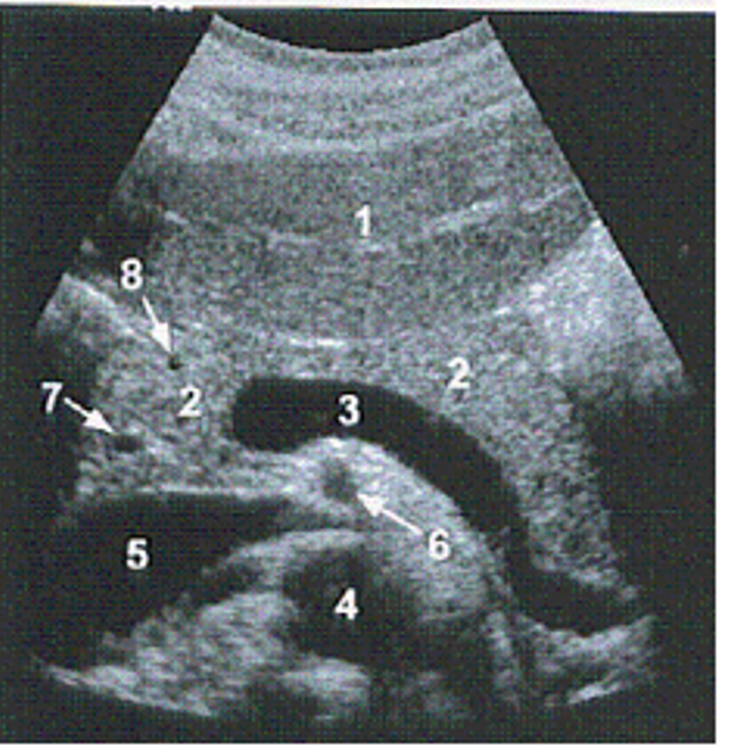

Identify the vessel labelled #6

SMA

The arrow is demonstrating which of the following vascular structures?

right renal artery